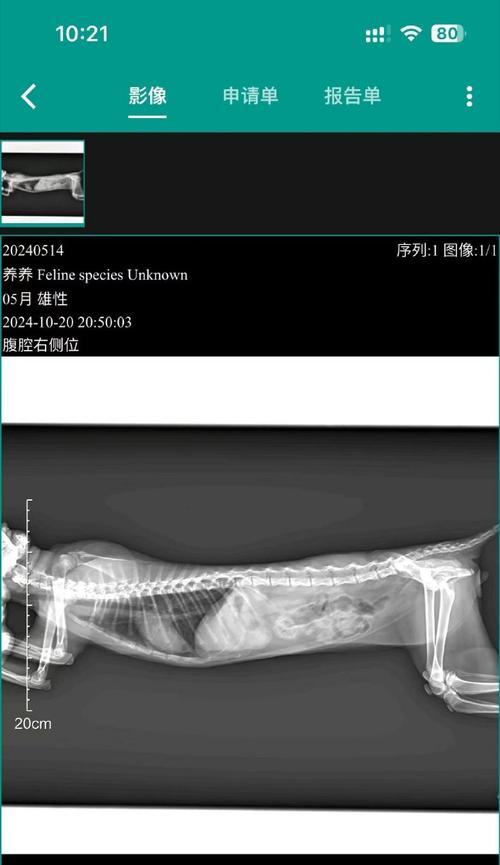

在这个阶段,胎儿的骨骼开始形成,进行X光检查可以更清楚地观察胎儿的发育情况。但仍需注意控制辐射剂量,以减少对母犬和胎儿的伤害。

在怀孕后期,胎儿已经基本发育完全。进行X光检查可以清楚地观察胎儿的位置和数量,并排除任何异常情况。